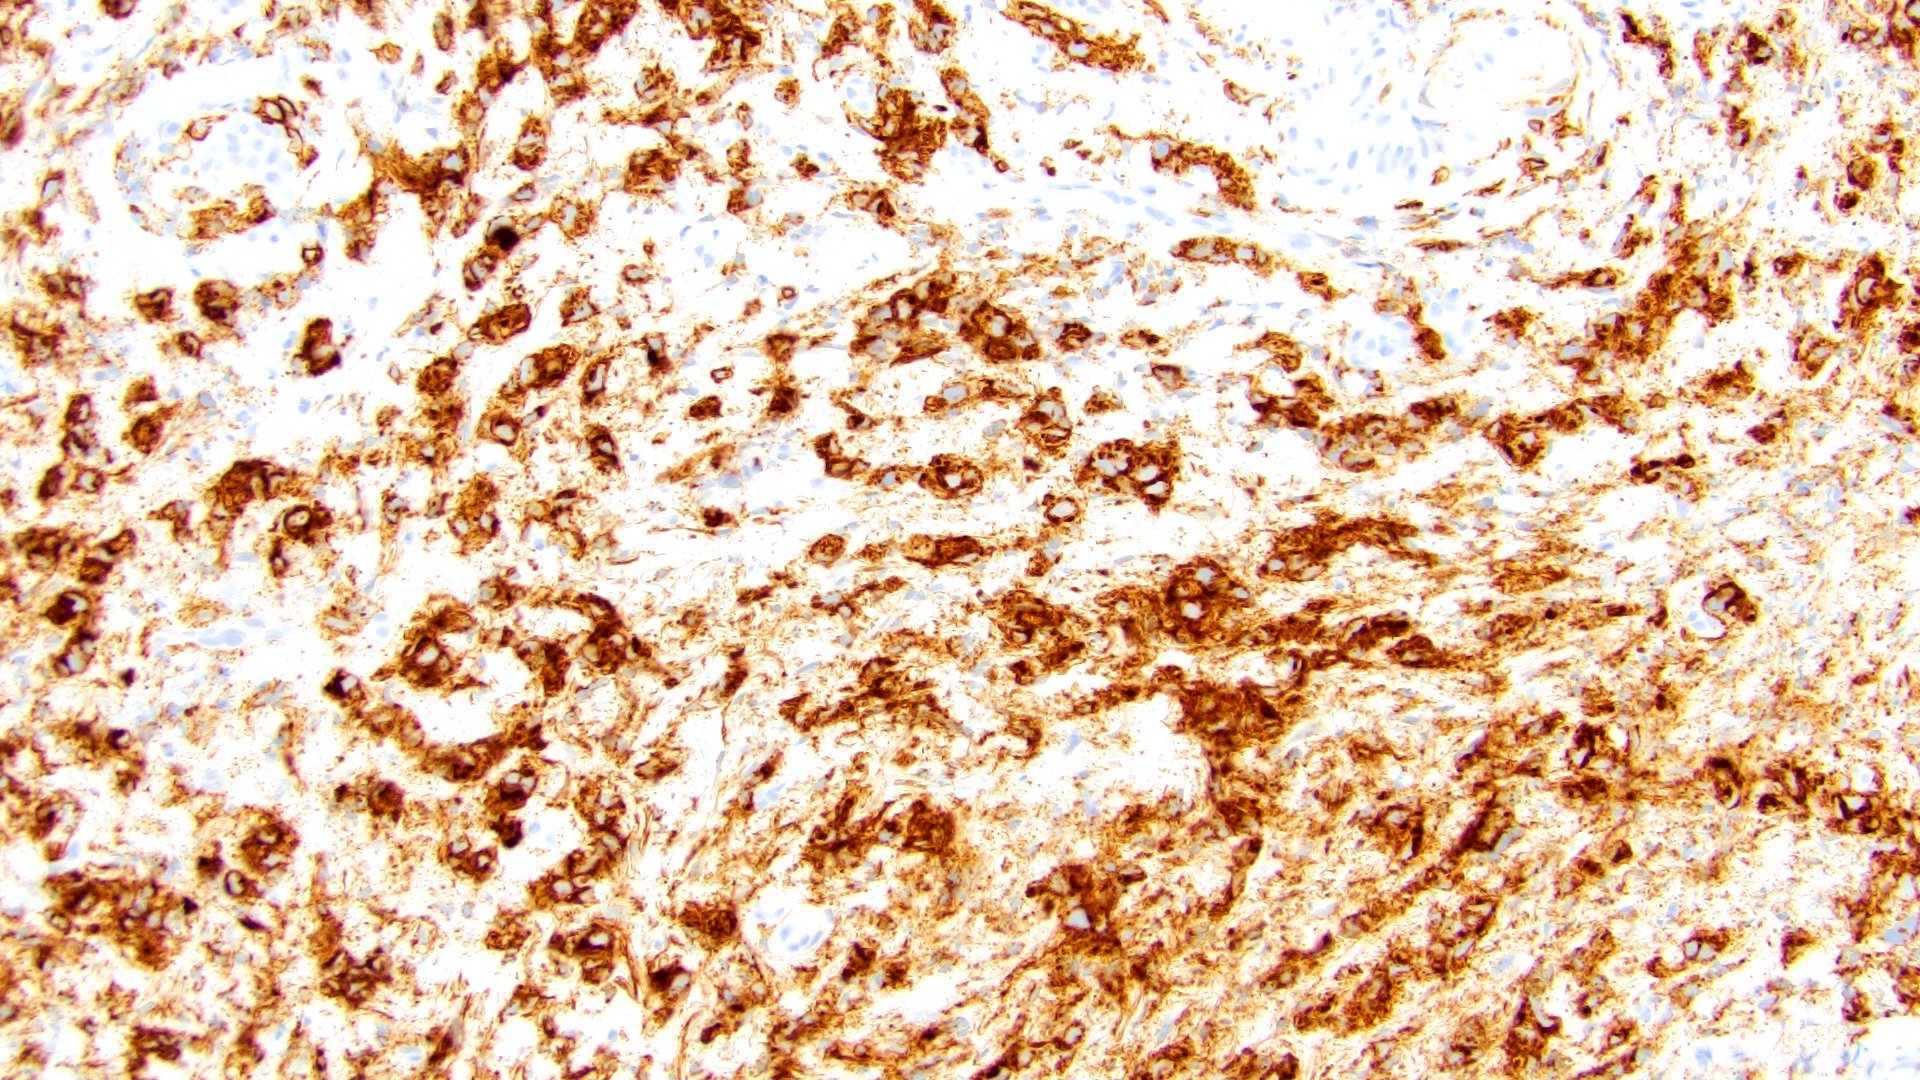

Microscopic (histologic) images

Contributed by Timothy Isaac Miller, M.D., M.A., Nicole K. Andeen, M.D. and Maria Tretiakova, M.D., Ph.D.

Contributed by Lisa Han, M.D. and Ricardo Lastra, M.D. (Case #510)

Negative stains

- E-cadherin (57 - 87% loss of membranous staining) (Hum Pathol 2019;90:27, BMC Urol 2020;20:72, Am J Clin Pathol 2017;147:500, Hum Pathol 2020;102:54, Int J Cancer 2011;129:346)

- p120 (73% had loss of membranous staining) (Hum Pathol 2020;102:54)

- 94% concordance with E-cadherin loss (Hum Pathol 2020;102:54)